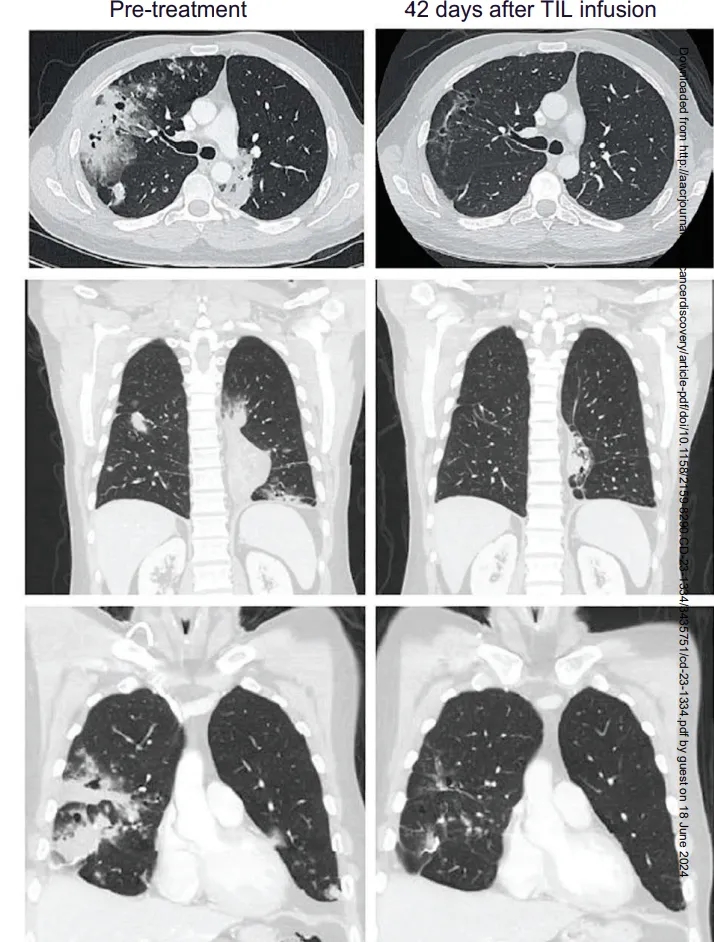

GC101是君赛生物自主研发的全球首款无需清淋预处理、无需IL-2注射的天然TIL细胞新药。2025年ESMO-IO大会首次公布其I期临床试验(NCT05417750)振奋数据:晚期非小细胞肺癌患者客观缓解率(ORR)41.7%(5/12,95%CI:15.2-72.3%),疾病控制率(DCR)66.7%(8/12,95%CI:34.9-90.1%,含5例部分缓解、3例疾病稳定),12个月总生存率高达66.7%(95%CI:33.7-86.0%)!

此外,国际顶级期刊《癌症探索》报道了lifileucel(Amtagvi)TIL疗法的振奋案例:41岁M先生确诊晚期粘液性肺腺癌(KRASG12D突变、PD-L10%),经卡铂+紫杉醇+派姆单抗三线治疗进展后接受TIL治疗,6周病灶显著缩小,12周肿瘤缩小81%!